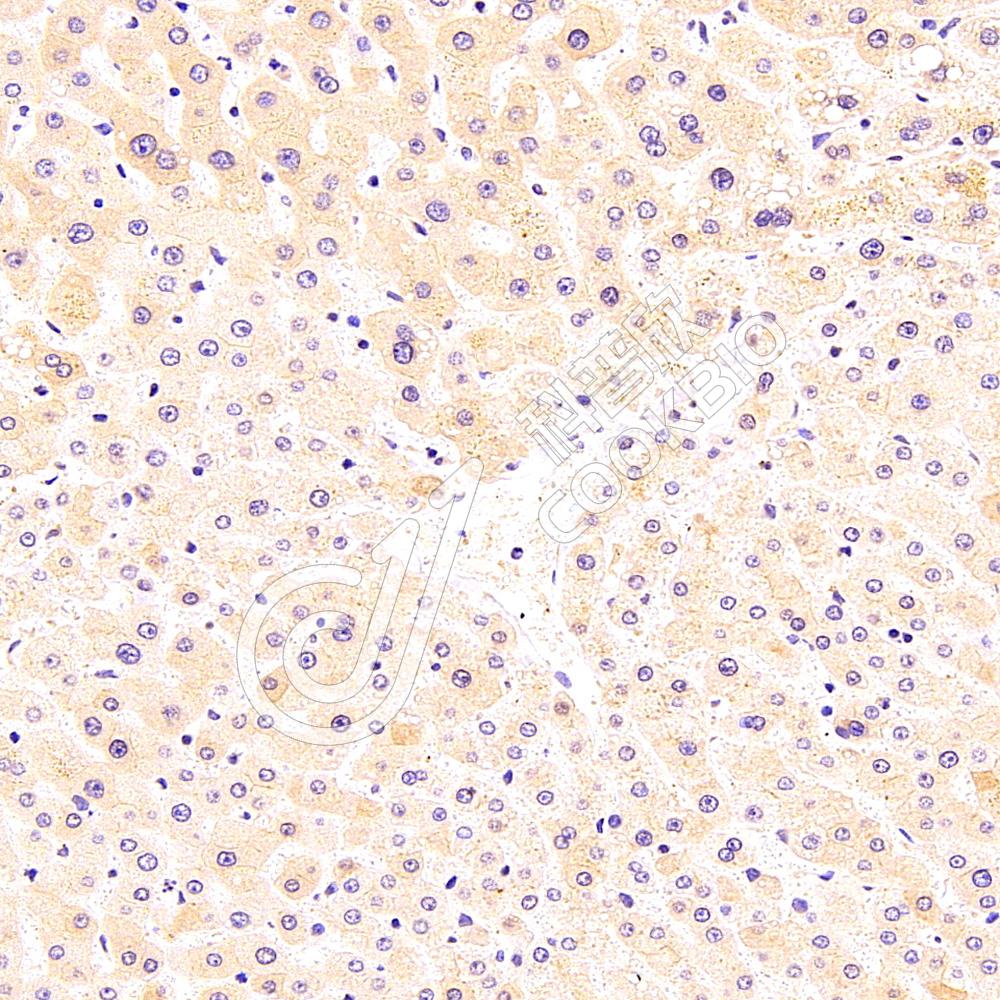

IHC检测MTHFD1蛋白(货号 K1336093).

样品: 人肝癌, 4%多聚甲醛 (货号KSG1101) 固定12-24小时.

抗原修复: 柠檬酸抗原修复液(干粉, pH 6.0) (KSG1201), 98℃, 20分钟.

—抗: 1: 1000稀释, 4℃ 孵育过夜.

二抗: S-vision免疫组化多聚二抗(山羊抗兔),即用型 (货号KB3906), 室温孵育20分钟.

样品: 人肝, 4%多聚甲醛 (货号KSG1101) 固定12-24小时.